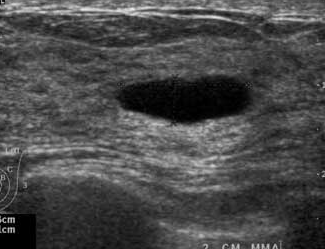

The target dataset was developed from 35 breast ultrasound scans that were segmented by an image-processing expert with extensive experience in breast lesion segmentation (the second author). The images, collected from the Web, are of different dimensions, ranging from to pixels (Figure 3, images resized for sake of illustration). These are the same images used to introduce EFIS originally [1].

Ultrasound images are generally difficult to segment, primarily due to the presence of speckle noise and low level of local contrast. It should be noted that the segmentation of ultrasound actually does require a complete processing chain, (including proper preprocessing and post-processing steps). However, the purpose of using these images was solely to demonstrate that the accuracy of the segmentation can be increased with the application of SC-EFIS.